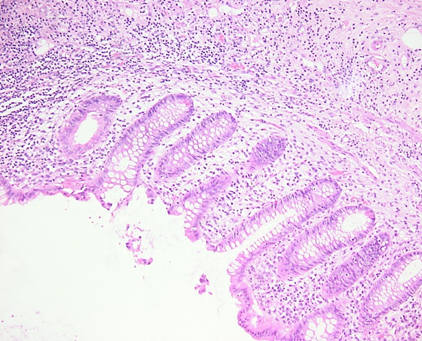

Abb.3: Histologisches Präparat der Appendixwand mit Fibrinauflagerungen als Zeichen einer Periappendizitis im Rahmen einer Typhlitis.